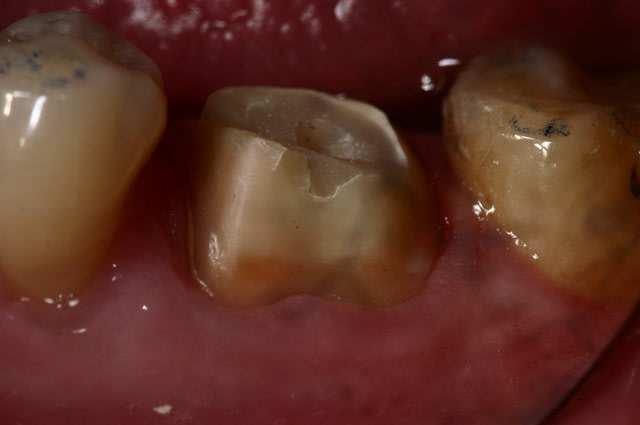

pour enfoncer le clou sur les tenons et autre inlay core

ne pas perdre de vue qu'un tenon = Rétention ... c'est tout !

Si on a de la rétention autrement, pas besoin de tenon...

Un tenon fragilise la racine et réduit l'étanchéité du traitement endo...

un cas comme on peut en faire souvent, d'endo couronne collée, exploitant le volume de la chambre pulpaire...

Et j'ajouterais que sur les photos que tu nous montres, tu as as réalisé un trottoir périphérique, pour réaliser qqchose qui ne correspond pas à la définition traditionnelle d'une endocouronne (qui est en réalité un onlay, avec prise de rétention interne).

Il est possible que l'ajout de férule par ce moyen permette au dispositif de fonctionner, mais dans ce cas, quel intérêt par rapport à une reconstitution composite avant couronne traditionnelle ?

C'est pas mal comme restauration, toutefois, tu as eu un peu de chance car l'endocouronne ne se prépare pas comme cela.

Tu a fais un mix entre la coiffe périphérique et l'endocouronne et il y a des risques de casse accrus. C'est dommage pour ces restaurations qui sont totalement inaltérables. Ce type de confusion dans les formes de préparations est très fréquent au début, et même un peu plus tard dans l'exercice. Il est certain que l'on a beaucoup de mal a lâcher les angrammes des restaurations classiques

Une endocouronne utilise le plancher caméral et sa forme de selle qui ne doit pas être fraisé et les parois sont ouvertes avec un maximum de 7° de TOC inversée.

La périphérie aplanie est si possible parallèle au plan occlusal ou perpendiculaire au sens d'application des forces.